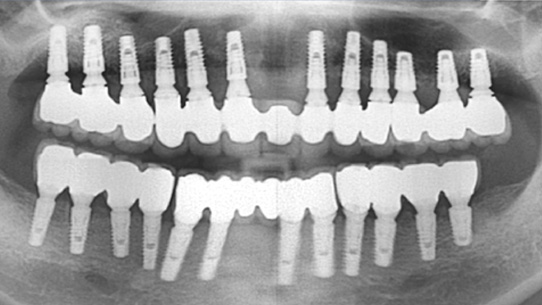

상악틀니를 사용 중 저작력이 약한 환자분. 대학병원에서 전체 임플란트를 받으시려 했으나 비용 문제로 고운미소로 내원하셨습니다.

당뇨수치가 있어 내과와 연계하여 식생활 조절과, 운동, 인슐린 치료를 병행하여 충분한 혈당관리를 하고

임플란트 수술을 시행하였습니다.

임플란트를 지지하기 위한 뼈의 상태가 좋지 않아, 상악동 뼈 이식과 함께 총 24개의 임플란트를 식립하였습니다.

전체 임플란트가 완성된 이후에도 내과와 지속적인 연계로 전신건강이 회복될 수 있게 노력해야 합니다.